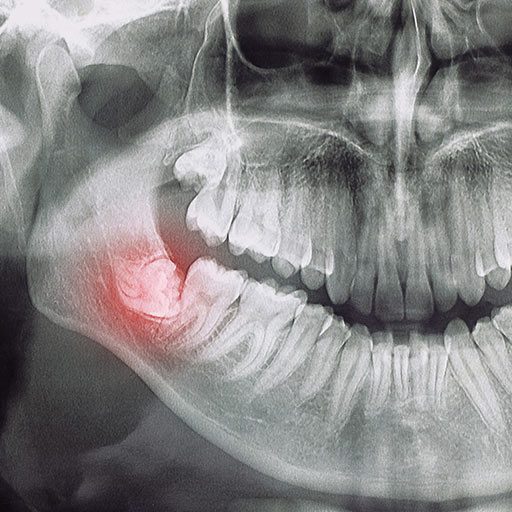

Zatrzymane zęby, najczęściej ósemki, to zęby, które nie wyrżnęły się prawidłowo i pozostają częściowo lub całkowicie ukryte w kości. Problem potrafi rozwijać się bezobjawowo, ale z czasem prowadzi do bólu, stanów zapalnych, obrzęku czy szczękościsku.

Planowe usunięcie zatrzymanej ósemki to bezpieczny i przewidywalny zabieg. Brak bólu nie zawsze oznacza brak problemu. Jeśli lekarz zaleca usunięcie zatrzymanego zęba, lepiej nie zwlekać. Zabieg w stanie zapalnym jest znacznie trudniejszy, a proces gojenia dłuższy i bardziej bolesny.

Informacje z internetu mogą być mylące – każdy przypadek jest inny. Dlatego najważniejsza jest konsultacja z chirurgiem stomatologicznym, który oceni Waszą sytuację na podstawie zdjęć RTG i badania klinicznego.

Następnie precyzyjnie zaplanuje całą procedurę i zarekomenduje moment przeprowadzenia zabiegu. Dla Twojego spokoju lekarz szczegółowo omówi z Tobą każdy jego etap.